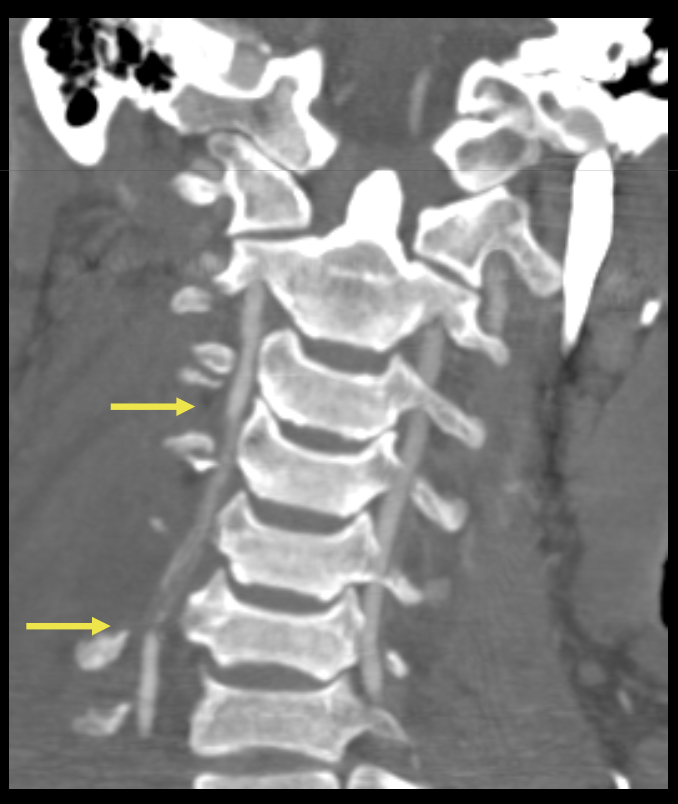

Que regarde-t-on ?

Une dissection vértébrale avec fracture du canal vertébral associé

Une lésion du rachis cervical C2